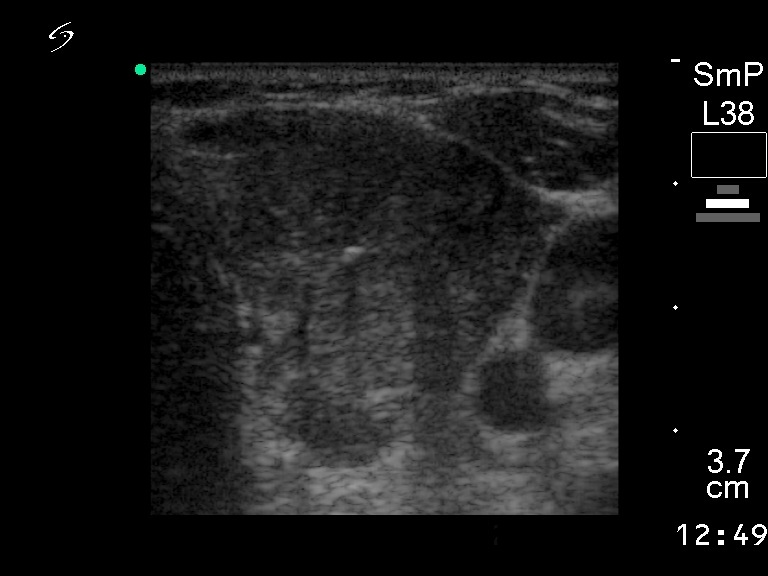

Papillary cancers - Case 56

Coarse calcifications are found more frequently in papillary carcinoma compared to benign lesions. This finding has only limited practical importance. In our study the difference did not reach the level of significance. Nevertheless, in certain cases the presence of microcalcification is of help in the diagnosis, e.g. in the last case demonstrated above. In this Hashimoto patient, several hypoechogenic lesions were present. One of them proved to be a papillary carcinoma; it was the only one which contained coarse calcifications.